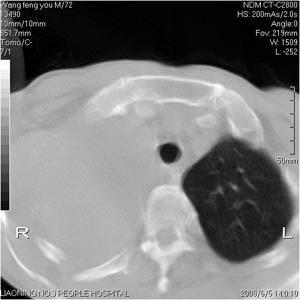

患者:男 72岁 右肩痛半年,近日来咳血,就诊.

右侧肺癌并肋骨破坏,右侧胸腔积液。

考虑:右肺上叶中心型肺癌伴肺不张、肋骨转移、肩胛骨转移、右侧胸腔积液。

右肺上叶全叶实变并不张,应为右上叶支气管阻塞所致。7、8层面好象是肋骨破坏。结合临床资料,考虑中央肺癌右上叶阻塞炎病及不张。左肺纤维化灶。右侧胸水。

抽胸水找癌细胞。

右侧肺上沟癌并肋骨转移,累及胸壁及胸膜。